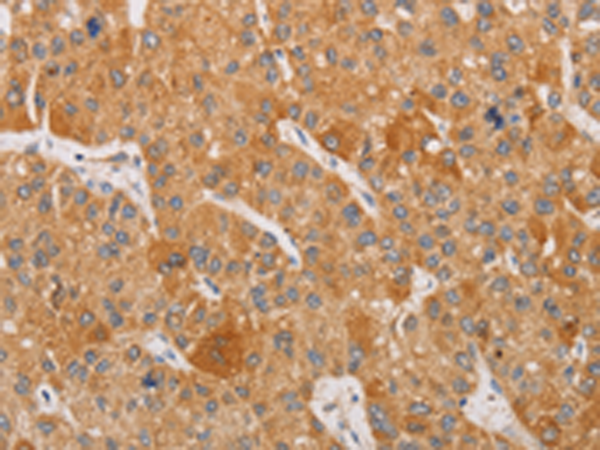

分类: 科研抗体货号: P08003别名: NIP3应用: WB,IHC反应种属: Human, Mouse